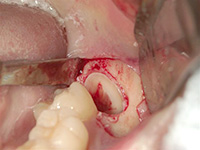

親知らずが非常に深い位置に、逆さの状態で埋まっていたケースです。右下7番の歯も保存不可能な状態だったため、抜歯しました。